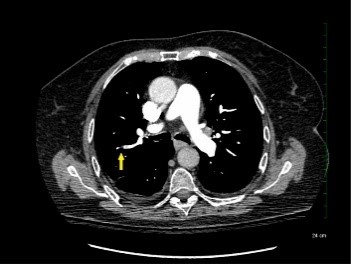

Due to advances in CT technology at emergency departments, more people are being diagnosed with 1-6 millimeter clots in the lung's smaller blood vessels, known as subsegmental pulmonary embolisms. However, it wasn't clear whether these clots were harmful, and some physicians will treat them while others will not.

The findings, published in Annals of Internal Medicine, show that patients with subsegmental pulmonary embolism are at greater risk of future blood clots, and should be treated with blood thinners.